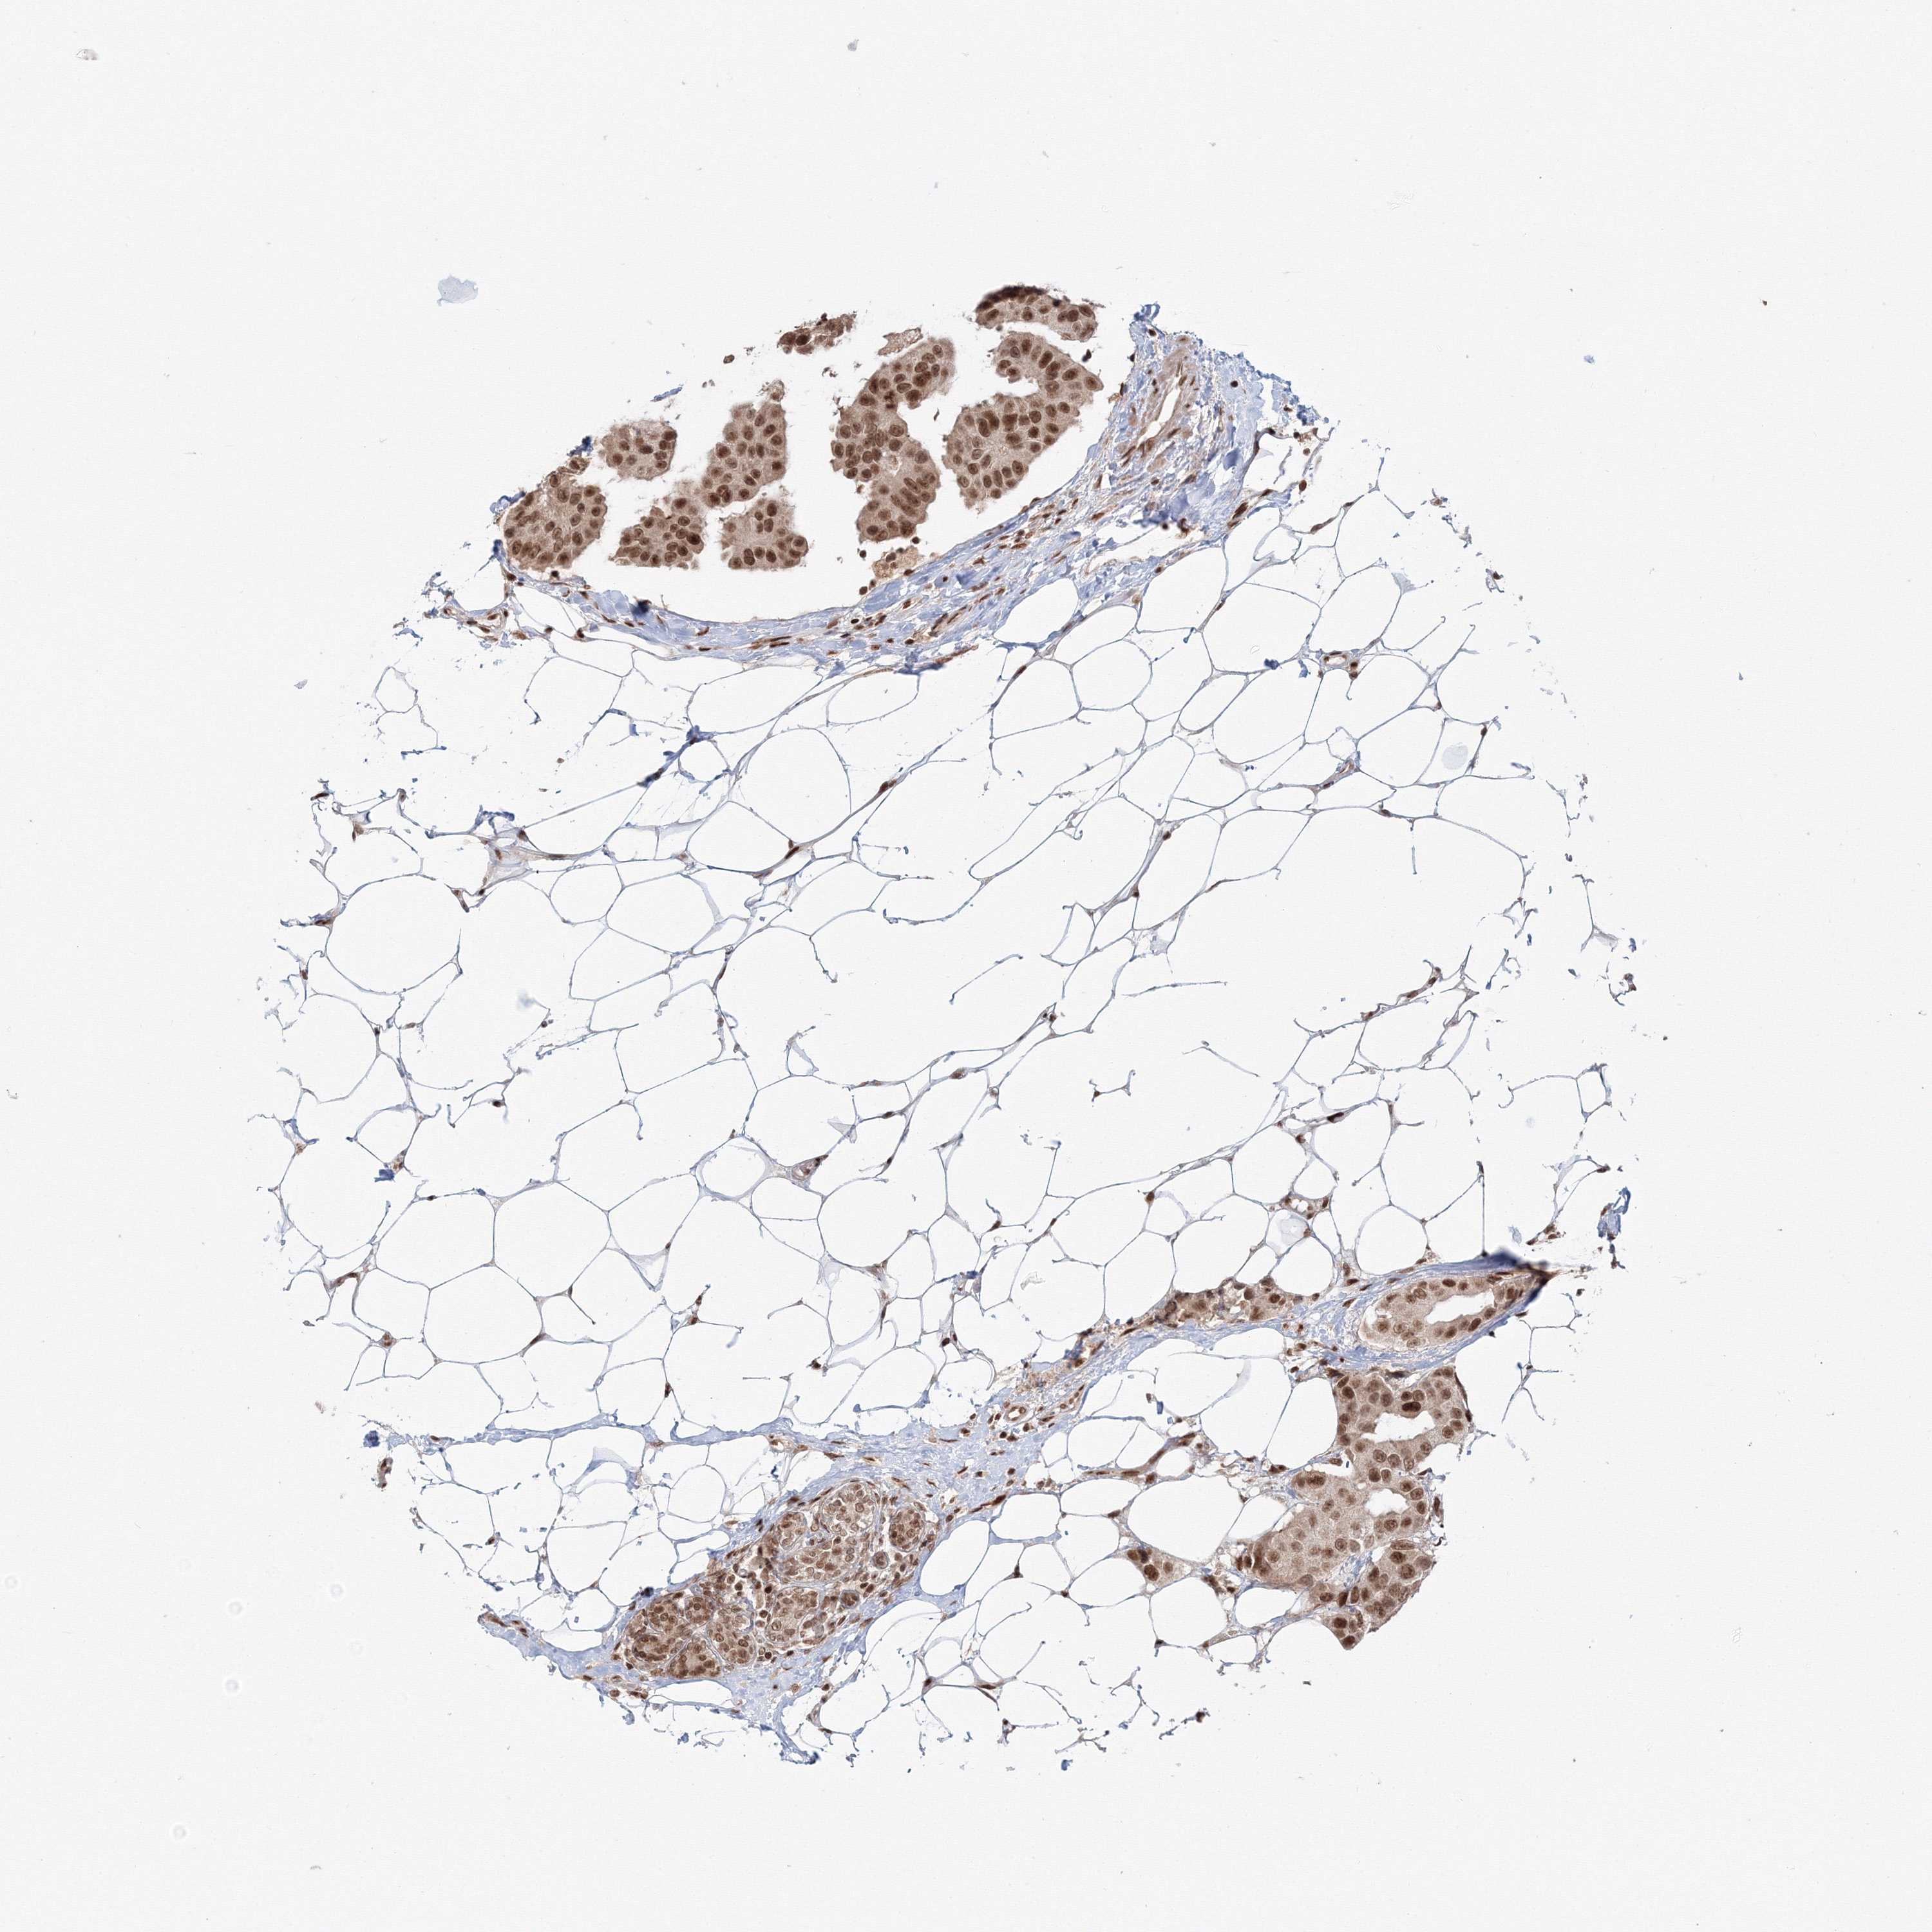

BRCA TCGA BRCA VALIDATION PROTEIN EXPRESSION